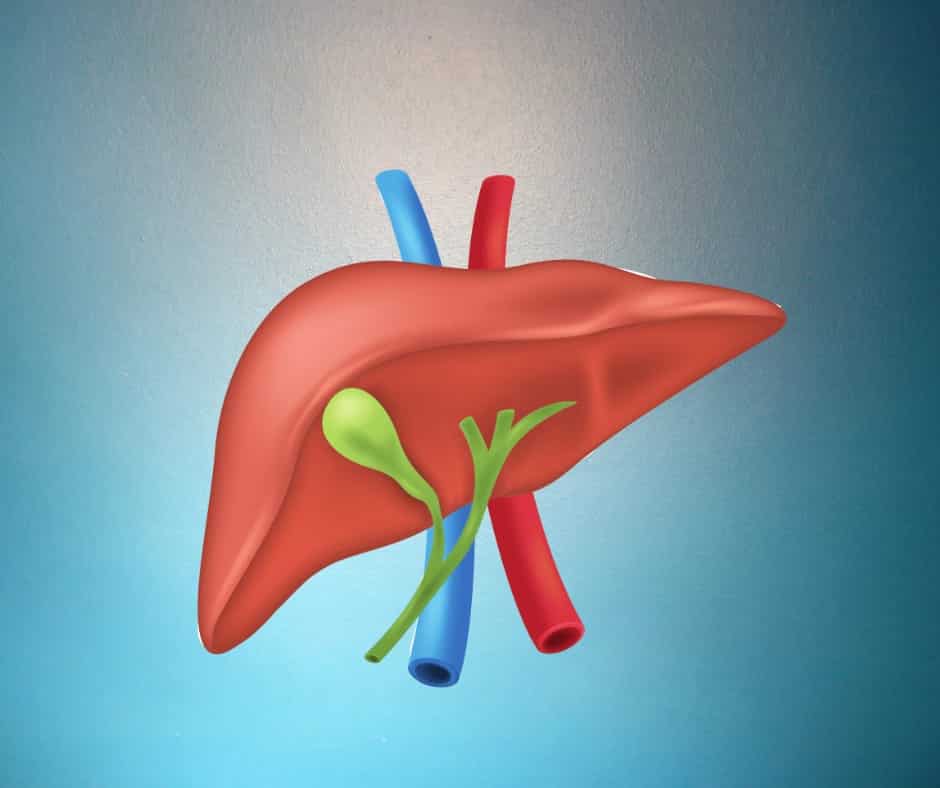

Liver function tests are advised by doctors to find out if the liver is functioning properly or if there is any problem with the liver. main liver function test bill Rubin Alkaline phosphate, AST/SGOT, ALT/SGPT, GGT, L proteins, albumin, globulin, and albumin/globulin can be detected through a liver function test.

Red blood cells in the body live for about 120 days and then die. when red blood cells die. Bilirubin is released. We call this indirect bilirubin. This indirect bilirubin goes to the liver and gets converted into direct bilirubin. If there is a liver problem, this bilirubin will increase; mainly the direct bilirubin will increase.

When any stones form in the liver, alkaline phosphate increases, which is a product of the liver itself. Alkaline phosphate increases during pregnancy. Bones release alkaline phosphate, which is why children have high levels of alkaline phosphate.

is elevated when there is any problem with the liver. AST is also produced by the liver, kidneys, and heart muscles.

Gamma-glutamate transaminase: if it is high, it can cause liver problems in people who drink alcohol.

The liver makes proteins for us. Who has liver problems? Total protein decreases, albumin decreases, and the AG ratio also decreases.